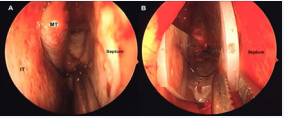

This technique also has the advantage of modification when the situation dictates. An example of a simple modification is the creation of an L-shape of the Silastic stent in the setting of very large septal flap harvest which includes the ipsilateral nasal floor. Another modification is the creation of a U-shaped Silastic stent used in the setting of concomitant septoplasty. In this situation, or in the situation where significant trauma occurs to the contralateral nasal or septal mucosa, U-shaped silastic stents are placed in the bilateral nasal cavities. This U-shaped modification allows the stent to cover the denuded portion of the nasal septum and floor, presses laterally on the inferior turbinate to ensure a good postoperative nasal airway and compresses the remaining septum in a midline position after septal reconstruction. We frequently use this modification (Figures 1).

(Figures 2).

Endoscopic intra-operative view of A: right nasal cavity after nasoseptal flap elevation, showing exposed septal cartilage, and B: Silastic stent placement, covering the denuded cartilage, floor of the nose and pressing laterallyon the ipsilateral inferior turbinate. MT: Middle Turbinate; IT: Inferior Turbinate.

Figure 2: Endoscopic intra-operative view of A: right nasal cavity after nasoseptal flap elevation, showing exposed septal cartilage, and B: Silastic stent placement, covering the denuded cartilage, floor of the nose and pressing laterallyon the ipsilateral inferior turbinate. MT: Middle Turbinate; IT: Inferior Turbinate.